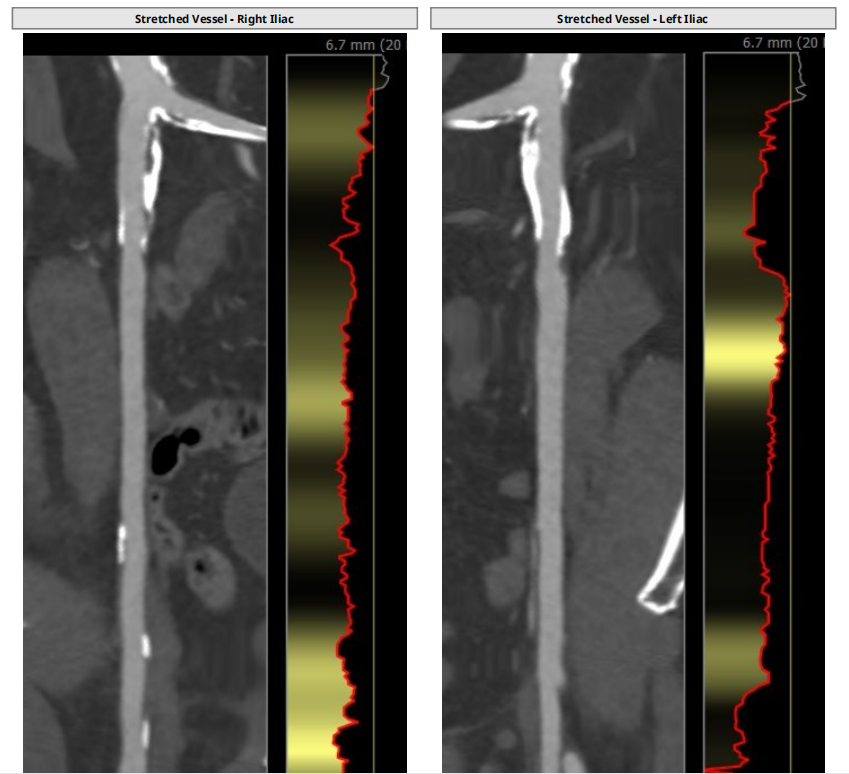

1、入路条件差,髂动脉血管钙化十分严重,通路建立难度极大。

1、因患者右股动脉钙化严重,入路狭窄,拟采取无鞘法从右股动脉建立通路。用18F大鞘尝试通过右股动脉可行,在无大鞘保护下送入输送器。

1、患者股动脉入路狭窄、钙化,通过评估和18F大鞘尝试后可采用无鞘法建立通路。